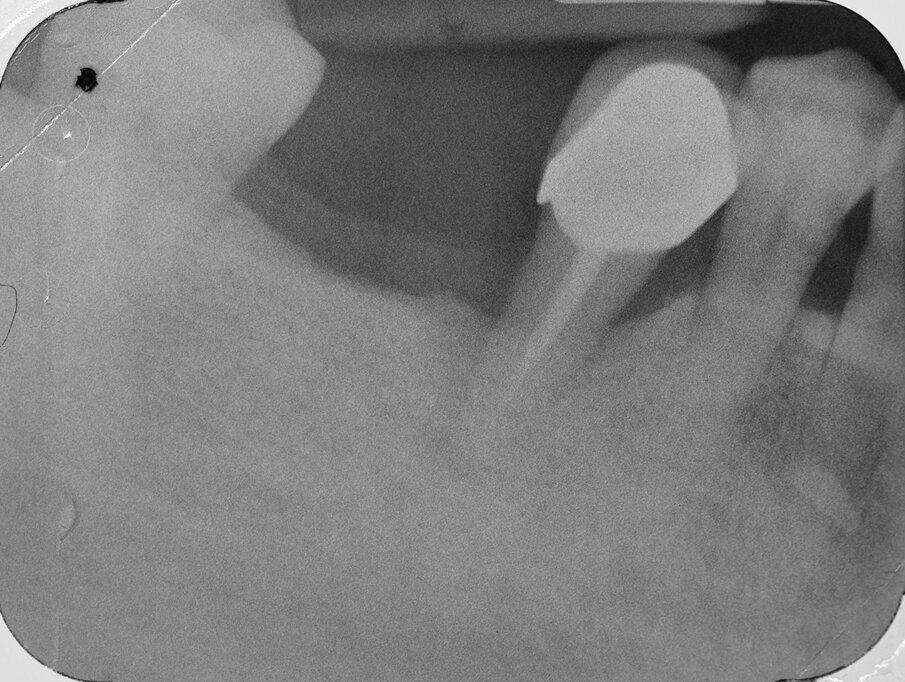

Paziente di aa. 62, femmina, giunge all’osservazione lamentando mobilità dell’elemento 4.5, dolorabilità e sanguinamento evocato durante le manovre di igiene orale (Fig. 1). Al sondaggio parodontale e all’esame radiografico endorale si evidenzia una consistente infiammazione del parodonto marginale associata a un vasto difetto intraosseo di tipo circonferenziale che interessa la superficie radicolare distale e buccale dell’elemento in oggetto (Figg. 2, 3). Al termine della terapia causale e della terapia parodontale non chirurgica il paziente è sottoposto a successiva rivalutazione, in base alla quale viene programmata una procedura di Rigenerazione Tissutale Guidata (G.T.R.) sull’elemento 4.5 associata ad inserimento di un impianto osteointegrato in sede 4.6. Poiché l’elemento dentario interessato dal difetto è adiacente ad uno spazio edentulo, la tecnica chirurgica di scelta è quella denominata “Crestal Incision”.

Al momento del controllo a 8 mesi vengono esaminate le condizioni dei tessuti parodontali marginali e si effettua una radiografia endorale periapicale, che evidenzia la completa risoluzione del difetto intraosseo (Figg. 17, 18). Incidentalmente, in occasione della scopertura dell’impianto precedentemente inserito, si sceglie di constatare de visu la rigenerazione ottenuta intorno all’ elemento 4.5: al sollevamento del lembo è possibile apprezzare la completa risoluzione del difetto intraosseo circonferenziale, a conferma di quanto già emerso dal controllo radiografico (Figg. 19, 21). Dopo aver esposto la testa dell’impianto in zona 4.6 si rimuove la vite di copertura, che viene sostituita con un healing abutment di adeguate dimensioni (Figg. 22, 23).